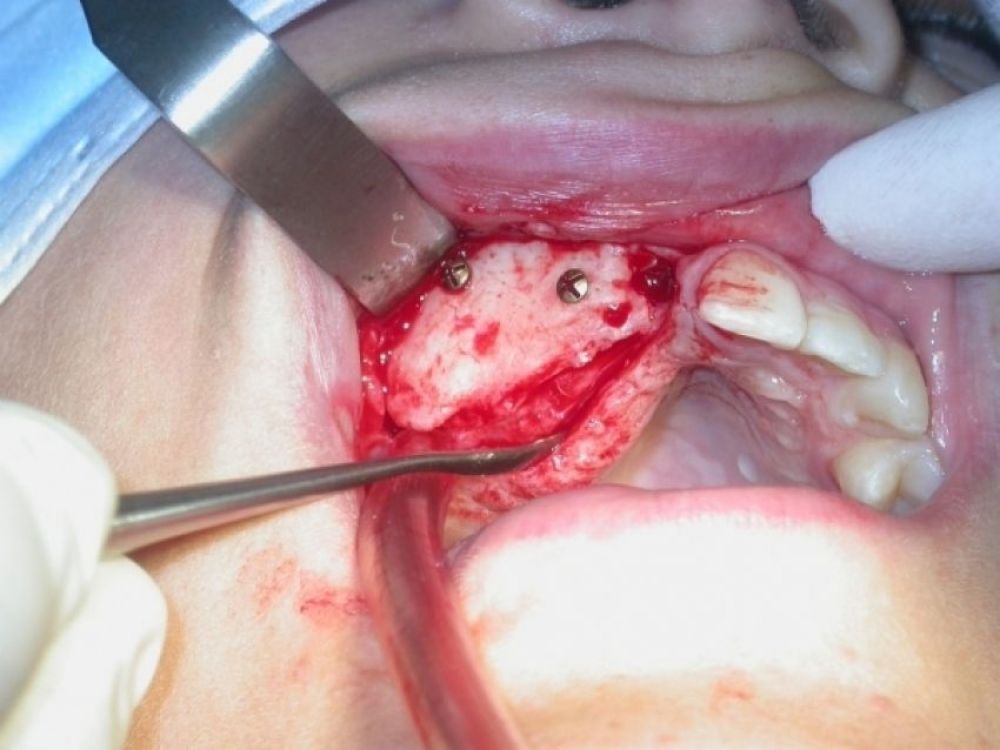

La diferentes técnicas quirúrgicas incluyen: el relleno óseo como por ejemplo en los casos de elevación del seno maxilar; los injertos de interposición (inlay) insertando material en el hueso alveolar para retomar los límites previos a la afectación ósea y; los de aposición (onlay) en los que colocamos directamente el hueso, habitualmente en bloques, sobre la zona a regenerar.

Los injertos más ampliamente utilizados hasta la actualidad y de manera prácticamente rutinaria, engloban: los obtenidos de la calota (parte externa del cráneo), cresta iliaca o cadera, mentón mandibular y diversas áreas de ambos huesos maxilares (rama ascendente de la mandíbula, tuberosidad maxilar… etc.). El mayor inconveniente radica en que tenemos que abordar una zona donante y ello provocará un cierto disconfort aunque éste, la mayoría de las veces será muy poco relevante, sobre todo si la comparamos con los beneficios obtenidos.